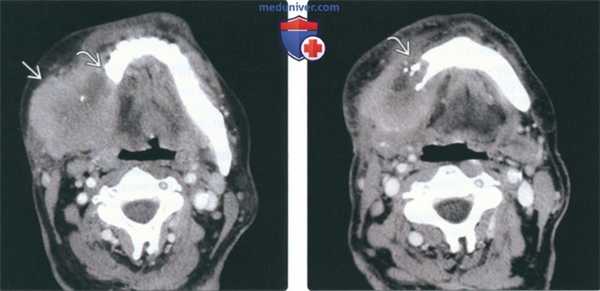

(Слева) КТ с КУ, аксиальная проекция. Злокачественная фиброзная гистиоцитома жевательного пространства и нижней челюсти. Солидная опухоль, которая умеренно накапливает контраст, располагается в правом жевательном пространстве и разрушает нижнюю челюсть, в том числе ее ветвь и тело. Жевательное пространство представляет собой глубокую область лица, в которой может возникать саркома.

(Справа) КТ с КУ, аксиальная проекция, тот же пациент. Солидная опухоль, умеренно накапливающая контраст, разрушает значительную часть нижней челюсти.

(Слева) На аксиальной КТ с КУ в жевательном пространстве справа визуализируется злокачественная фиброзная гистиоцитома нижней челюсти в виде минимально контрастирующегося солидного объемного образования, разрушающего ветвь и тело нижней челюсти. Жевательное пространство является известным местом возникновения сарком глубоких областей ли ца.

(Справа) На аксиальной КТ с КУ у этого же пациента визуализируется опухоль в жевательном пространстве справа, приводящая к обширной деструкции нижней челюсти. Обратите внимание на асимметрию лица на стороне поражения.